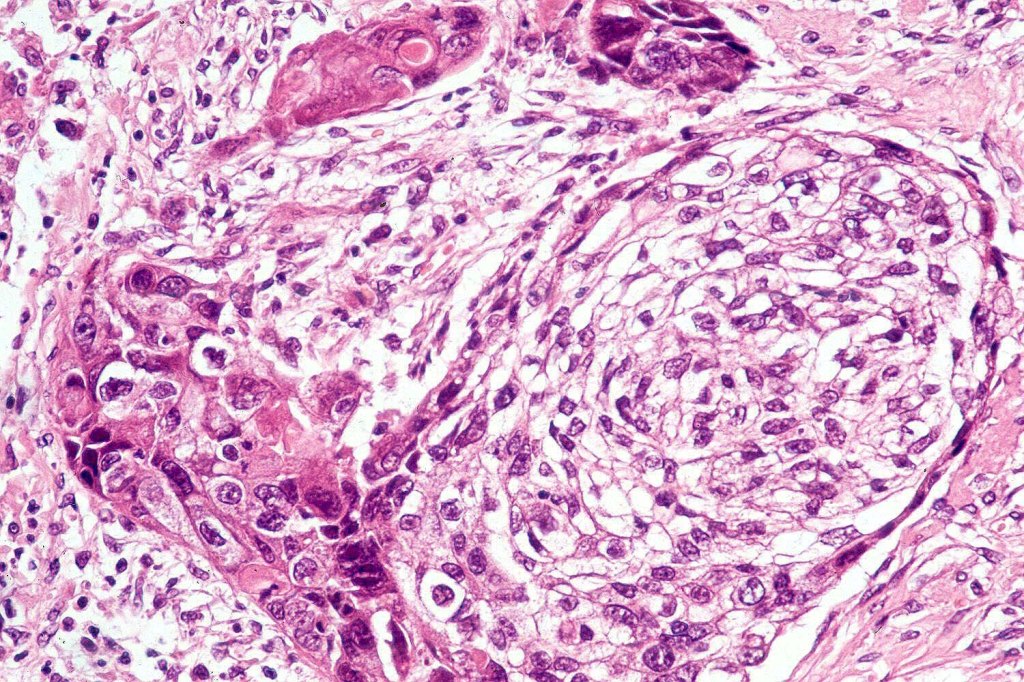

Histological features

•Clear cell change results from cytoplasmic glycogen accumulation

•Can be focal or involve most of the tumor

•Exceptionally, this can present with a signet ring-like appearance